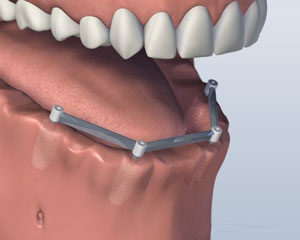

酒吧附着体义齿

另一种选择涉及将四到六种植体, 这取决于你的下巴大小或形状, 进入你的下颚. 后完全愈合, 植入物与一个特制的支撑杆连接. 你的假牙将与附着到支撑条特殊的内部固定夹进行, 使假牙牢固卡入到位. 这就是所谓的 “覆盖义齿.” 这个方案的优点是,它更稳定比第一个选项,允许非常小的义齿运动. 你的义齿仍然是可拆卸,便于清洁和维护.

1. 之前

2. 植入放置

3. 义齿附